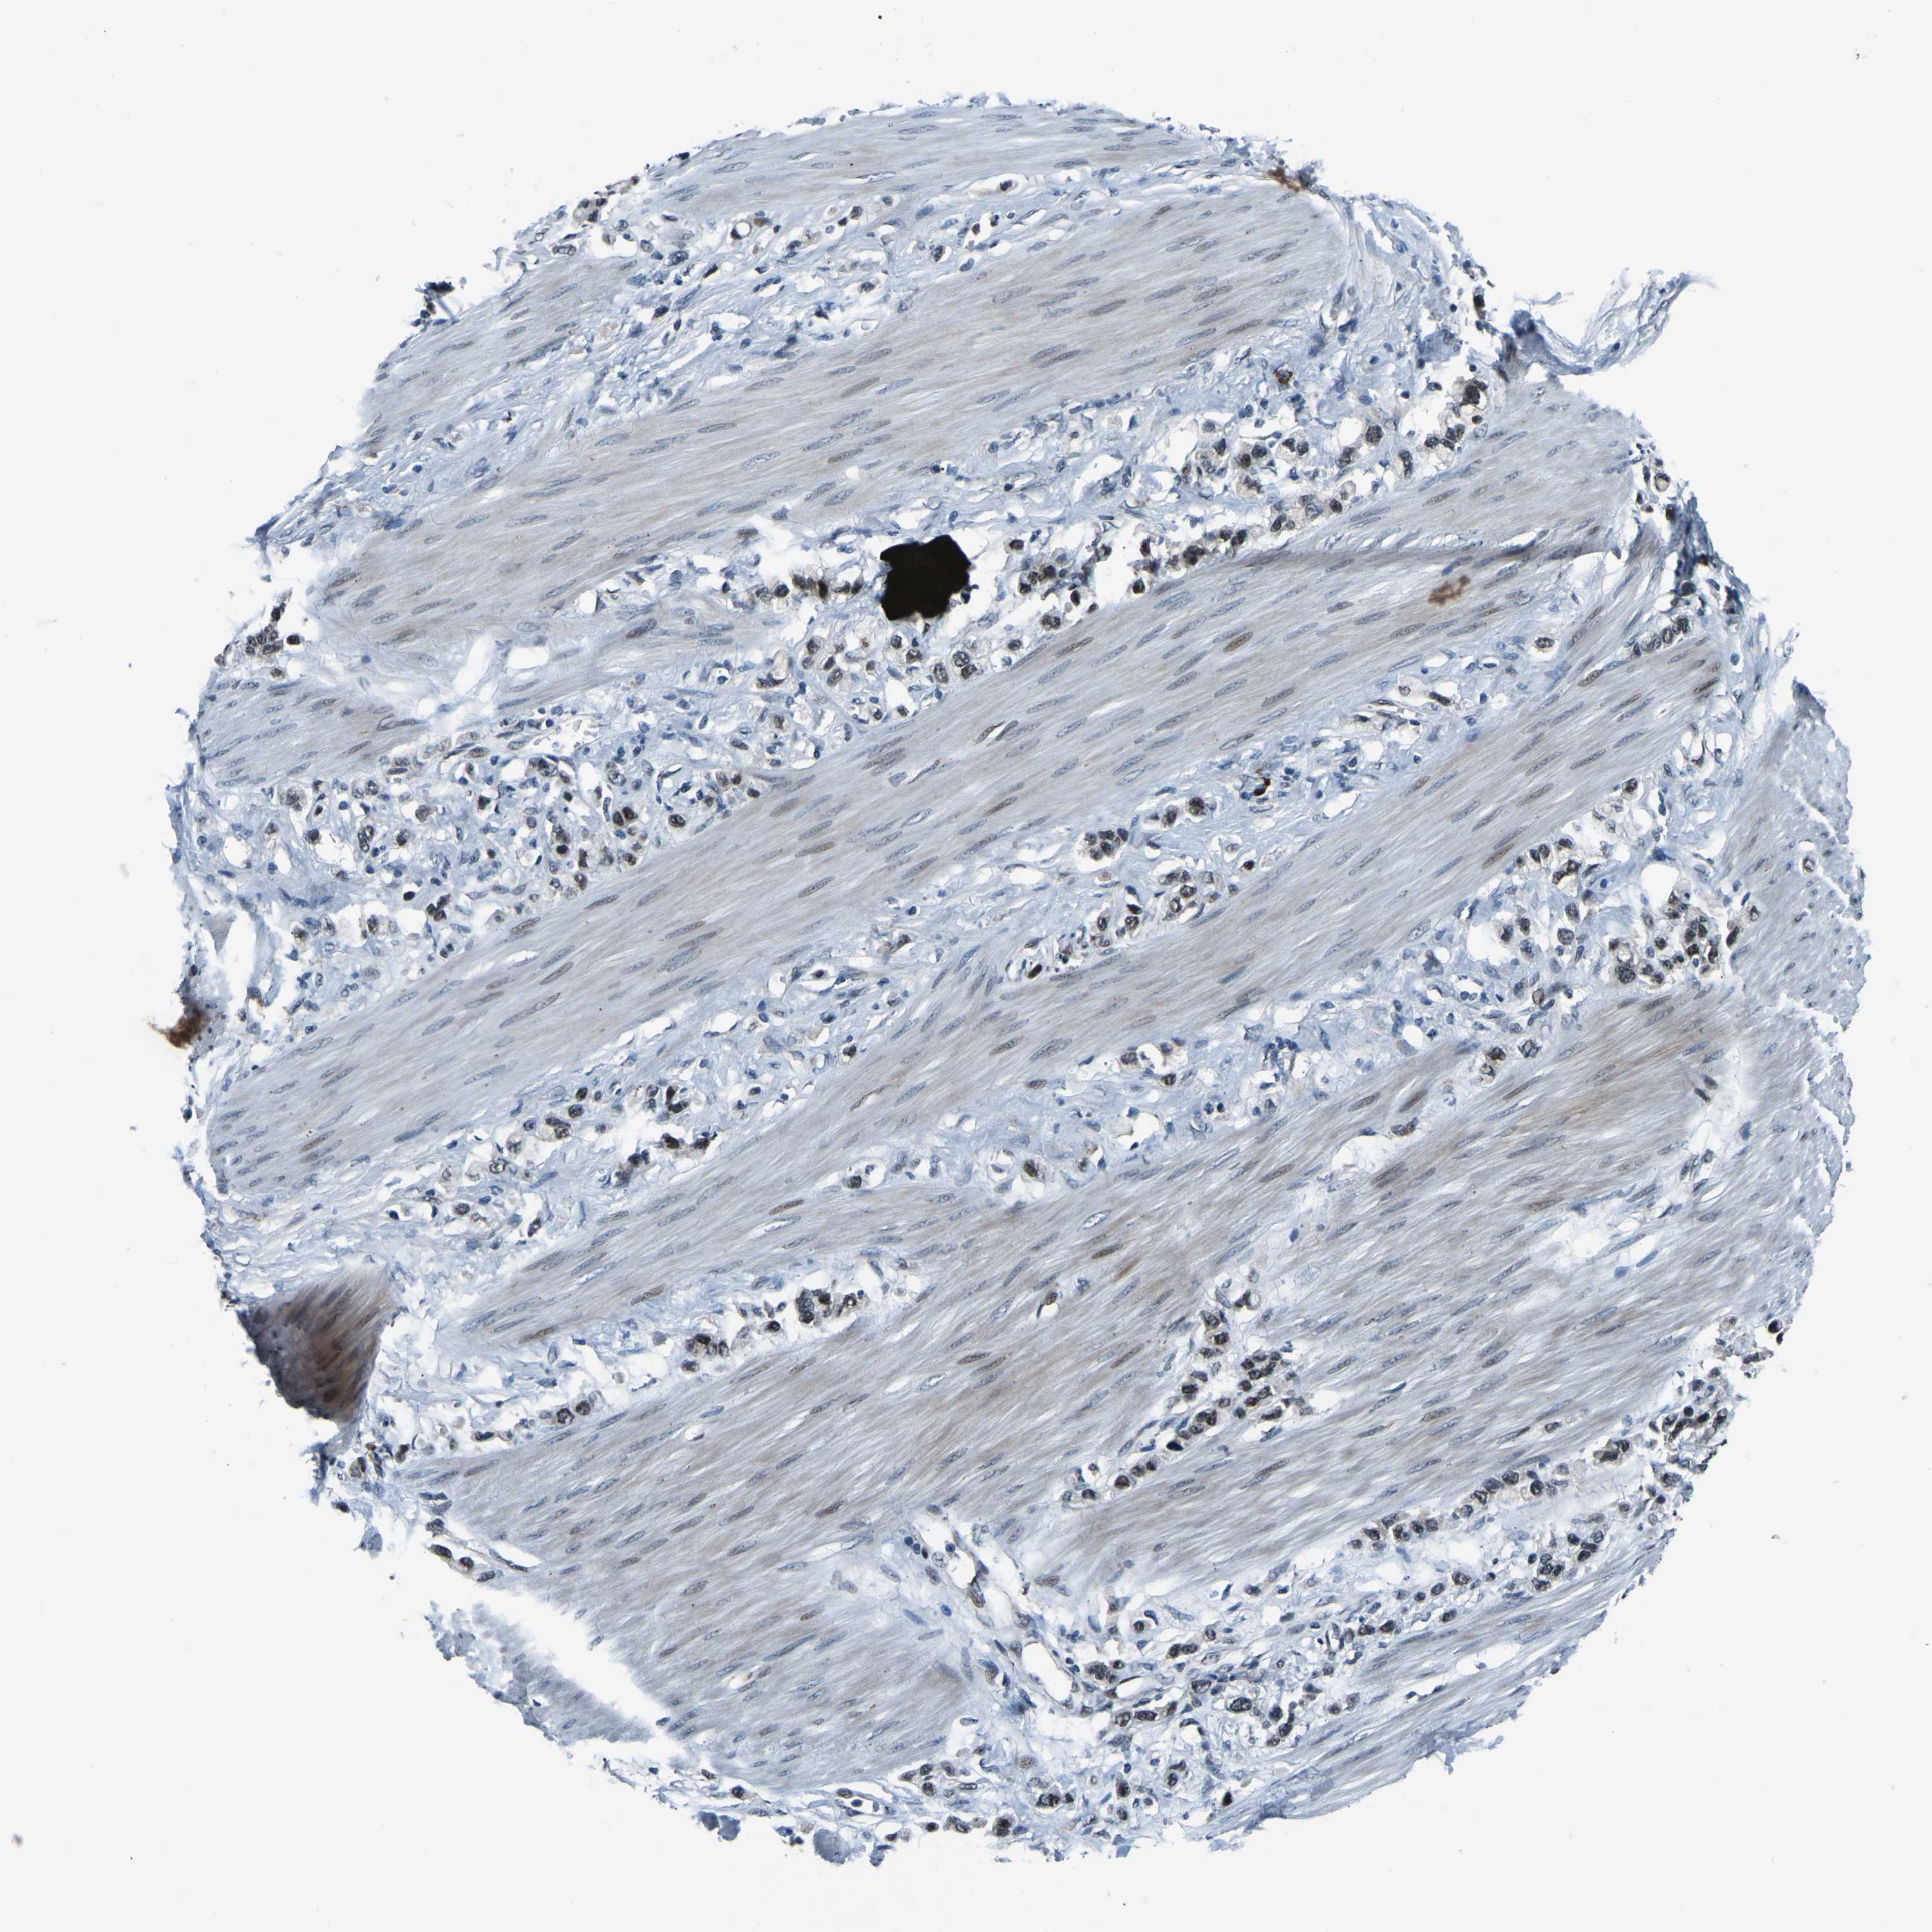

STOMACH CANCER - Protein expressioni

A mouse-over function shows sample information and annotation data. Click on an image to view it in a full screen mode. Samples can be filtered based on level of antibody staining by selecting one or several of the following categories: high, medium, low and not detected. The assay and annotation is described here.

Note that samples used for immunohistochemistry by the Human Protein Atlas do not correspond to samples in the TCGA dataset.

Antibody stainingi

Antibody staining in the annotated cell types in the current human tissue is reported as not detected, low, medium, or high, based on conventional immunohistochemistry profiling in selected tissues. This score is based on the combination of the staining intensity and fraction of stained cells.

Each image is clickable and will lead to virtual microscopy that enables deeper exploration of all samples and also displays staining intensity scores, fraction scores and subcellular localization as well as patient and tissue information for each sample.

Antibody HPA019486

Antibody HPA021517

Staining

High

Medium

Low

Not detected

Intensity

Strong

Moderate

Weak

Negative

Quantity

>75%

75%-25%

<25%

None

Location

Nuclear

Cytoplasmic/membranous

Cytoplasmic/membranous,nuclear

Adenocarcinoma, NOS